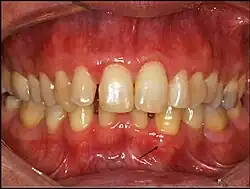

Gingival cyst of adult is a rare condition. The incidence is less than 0.5%. It is formed from the rests of dental lamina.[11] It is found in the soft tissues on the buccal and labial portions of the jaw. It usually occurs on the facial gingiva as a single small flesh colored swelling, sometimes with a bluish hue due to the cystic fluid. Sometimes, it may occur in cluster, either unilaterally or bilaterally or on the lingual surface of the alveolar process. It is most commonly seen in the canine and premolar regions of the mandible, and are sometimes confused with lateral periodontal cysts.[12] It is not normally problematic, but when it grows larger, it can cause some discomfort. It can be removed by simple surgical excision. They are developed late in life, generally up to the sixth decade of age.[1]